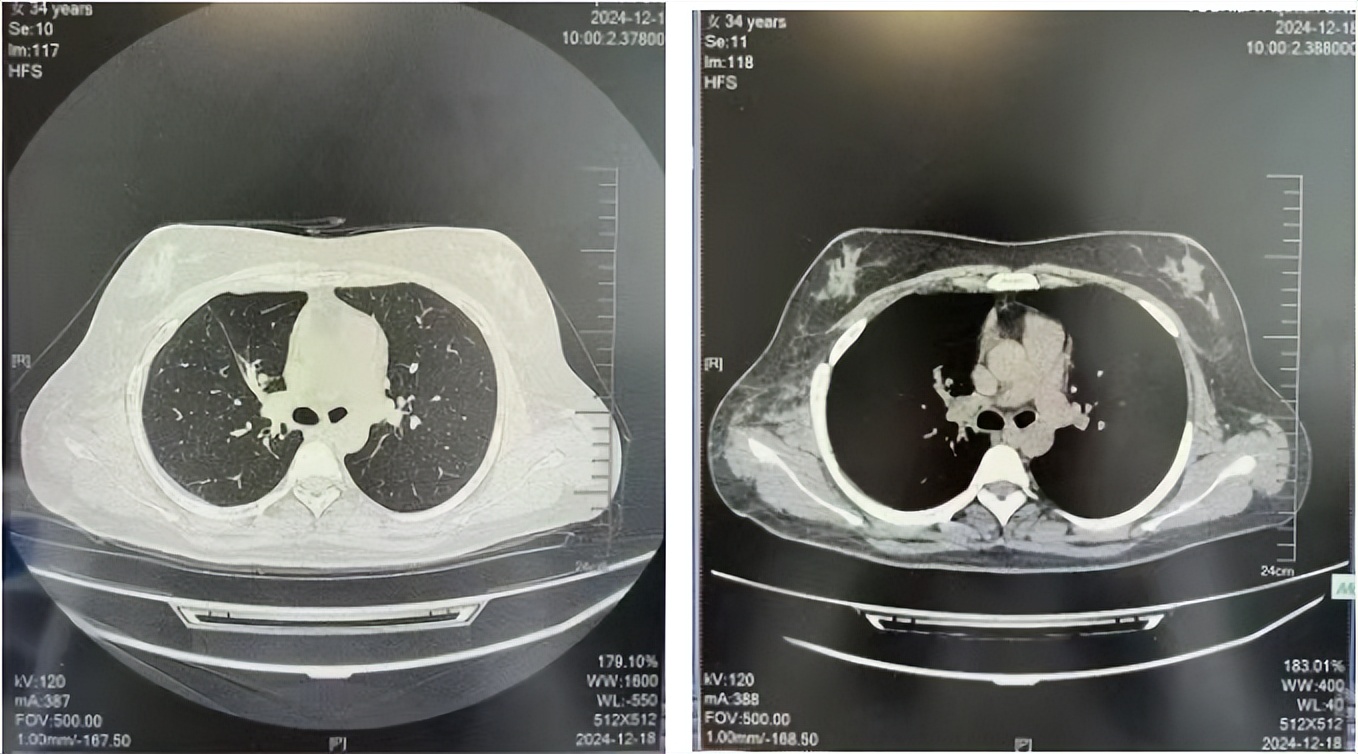

34岁,女性,无吸烟史饮酒史,既往体健。2015年11月无明显诱因出现咳嗽咳痰,痰为黄色粘液状,就诊于铁西华康医院,胸部CT示右肺上叶尖段可见结节影,邻近胸膜局限牵拉。2015年12月于胸科医院行肺肿物穿刺活检病理回报为肺腺癌。2015年12月16日全麻下行右肺上叶肺癌根治术及纵隔淋巴结清扫术,术后病理:肺组织中部分脉管内见腺癌组织,断端支气管旁淋巴结内见癌组织,淋巴结中见到转移癌(2/6),未行基因检测。

2016年1月复查CT提示支气管截断可见新发小结节,一线治疗采用培美曲塞+DDP方案化疗4周期(培美曲塞3.36,DDP 480mg)。化疗后复查胸部CT:右肺见不规则结节样影,最大层面大小约19mm*8mm,较前比较明显增大,疗效评估PD。2017.3-2017.4予单药多西他赛化疗3周期,疗效评估SD。2018年5月末复查CT提示结节较前增大,评效为PD,2018年6-10月予多西他赛+CBP化疗4周期,疗效评估SD。2022年5月患者出现活动后气短,复查胸部CT示右肺膨胀不良;右侧胸腔积液增多。胸腔积液包埋病理示符合肺腺癌细胞。行NGS基因检测:EML4:exon13-ALK:exon20融合。PD-L1(克隆号22C3)TPS<1%。

临床诊断:右肺上叶恶性肿瘤rT0N0M1a IVA期(第9版分期);恶性胸腔积液。

诊疗经过:2022年5月始口服克唑替尼3个月,出现肝功能异常(DILI 2级伴临床症状),改用恩沙替尼靶向治疗至今,目前评效为维持PR。恩沙替尼应用期间出现轻度肝功能异常(DILI 1级),对症处理后好转。截止目前PFS 33个月。

2024.12